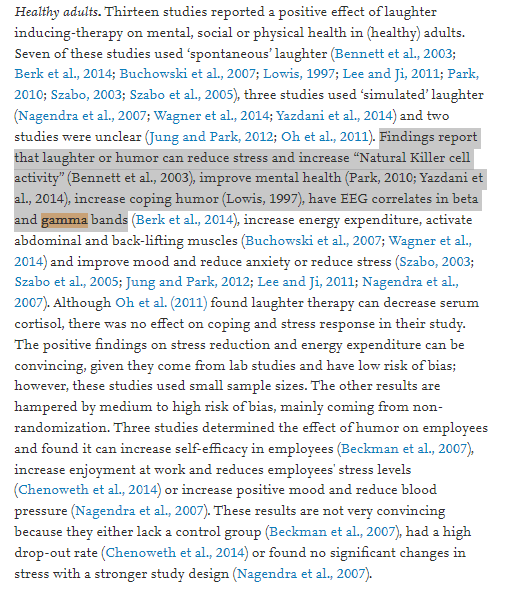

Laughter and meditation fix gamma waves too AFAICT. It's funny to look at laughing yogi(?) in india. They are all able to live until they are quite old. They attrib to laughter too IIRC. https://t.co/wWNt0XVZh0https://t.co/eCYwo8ONz5 https://t.co/dpgGFiB5mR

Laugh with me."What this means is that humor actually engages the entire brain -- it is a whole brain experience with the gamma wave band frequency and humor, similar to meditation, holds it there; we call this being 'in the zone,'"https://t.co/pVV5iLMpMw https://t.co/qPRaT80N4x